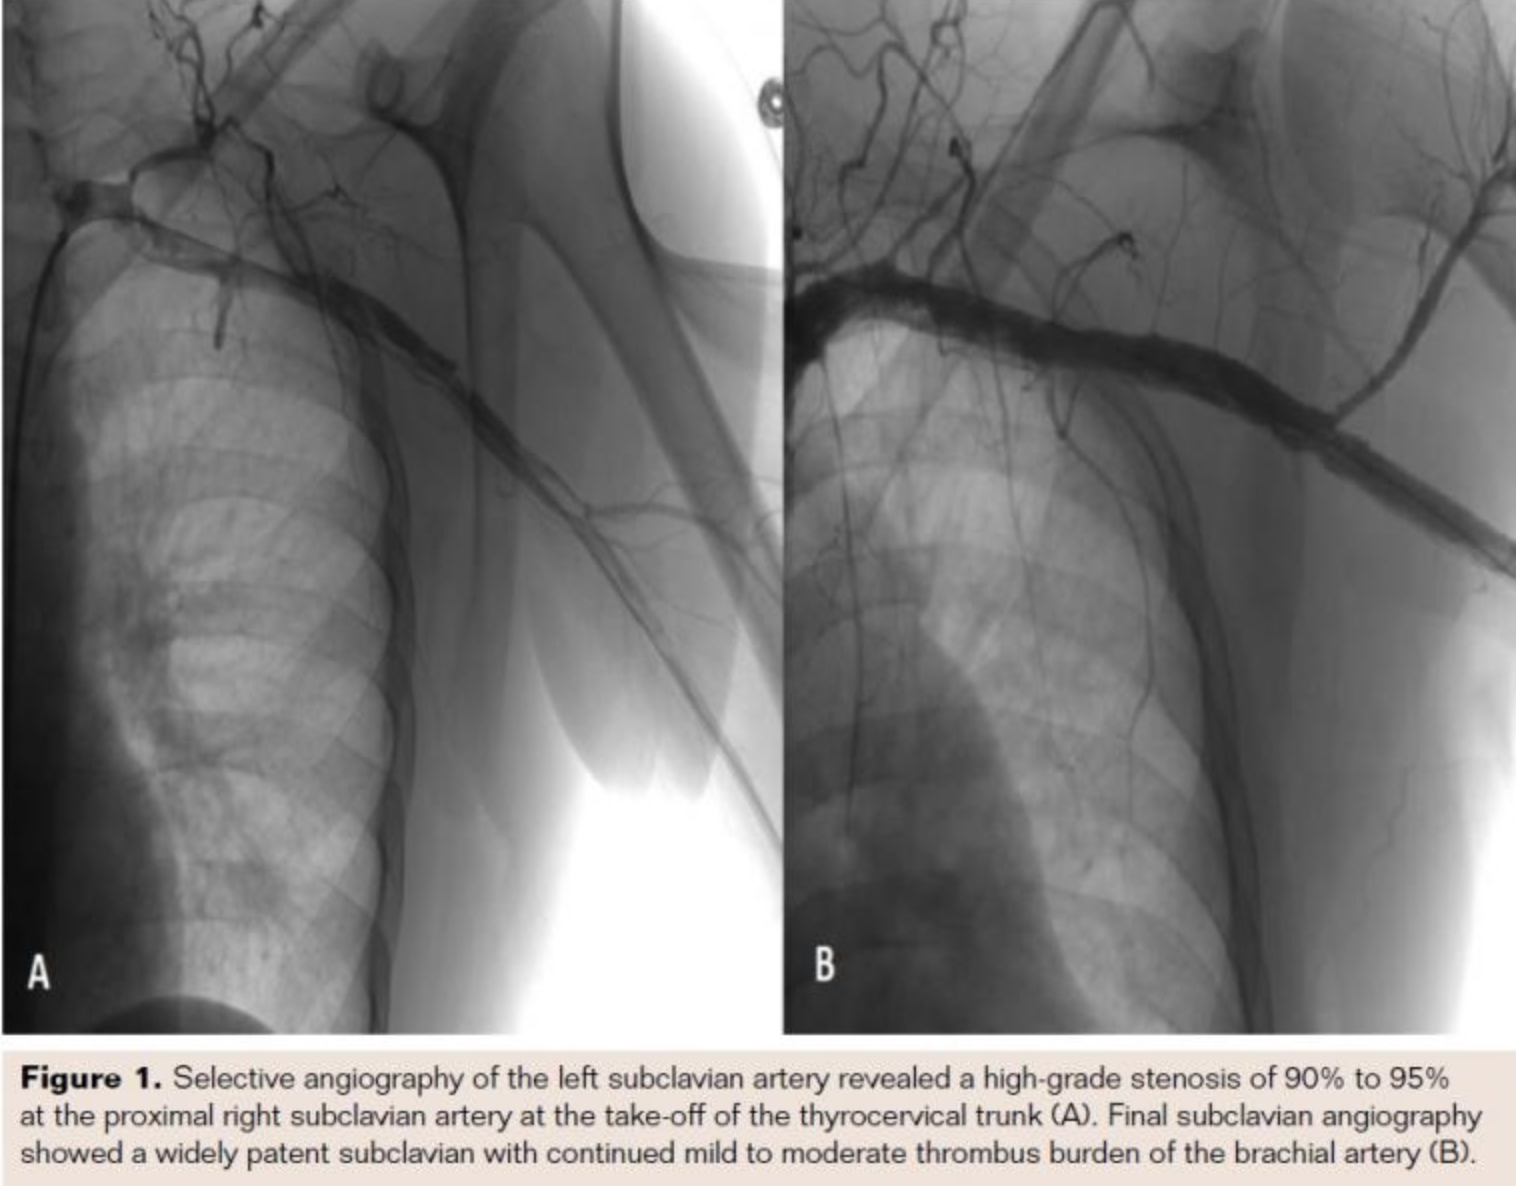

Aortogram revealed a type 1 arch with a patent right innominate artery and left vertebral and carotid artery. Selective angiography of the left subclavian artery revealed a high-grade stenosis of 90% to 95% at the proximal right subclavian artery at the take-off of the thyrocervical trunk (Figure 1A). The flow distal from the stenosis was extremely sluggish, and further angiography revealed severe stenosis with heavy thrombus burden in the proximal axillary and brachial arteries. Due to the significant thrombus burden, the decision was made to utilize a .035˝ 6 Fr Angiojet (Boston Scientific) in an attempt to perform thrombectomy by making multiple passes through the artery. The lesion was carefully crossed with a stiff angled glidewire and this wire was then subsequently exchanged for a Wholey wire. Repeat angiography after thrombectomy revealed significantly improved flow within the subclavian and axillary arteries but continued heavy burden in the brachial.

At this point, it was determined that the next course of action would be to perform balloon angioplasty of the brachial artery and 2 inflations were done with a 5 mm x 80 mm balloon. Final subclavian angiography showed a widely patent subclavian with continued mild to moderate thrombus burden of the brachial artery (Figure 1B). Because of this the patient was transferred back to the cardiac care unit with a tPA infusion through a catheter placed in the left brachial artery. At this time, his left arm pain had resolved and there were pulses identifiable by Doppler in the left radial and ulnar arteries. The next day, angiography confirmed a widely patent artery, so the infusion catheter and sheaths were removed. It was initially thought that the patient had presented with an acute vasculitis, but laboratory studies showed that his ESR and CRP were within normal limits. Once the patient was stabilized, he was transferred to a tertiary center where he underwent genetic testing and was diagnosed with type IV Ehlers-Danlos syndrome.